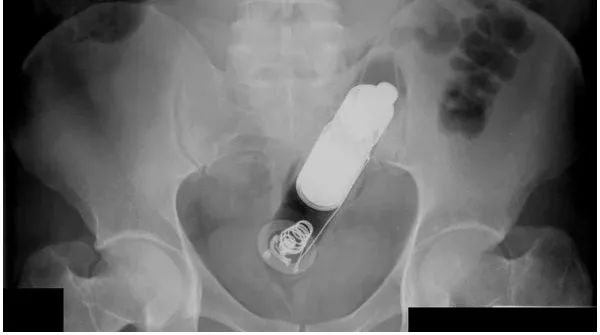

又到了大家最喜歡的看圖猜異物環節

請將答案按順序寫在評論區